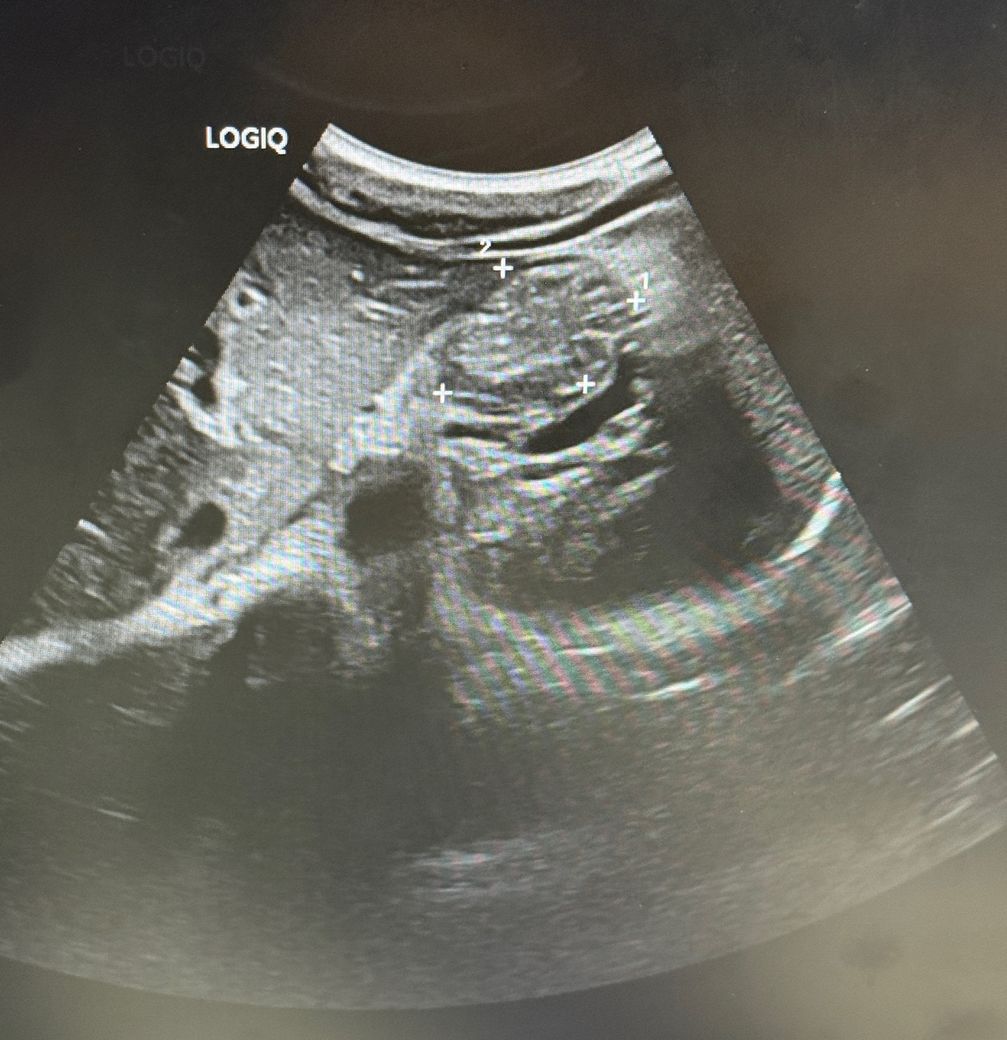

왼쪽 상복부쪽 덩어리가 느껴져요 초음파와 ct를 받았는데 원인을 모르겠다고 합니다.

좌측 갈비뼈쪽 아래에 통증이 느껴지면서 약간 덩어리가 만져지고 엎드렸을 경우에는 확실하게 무언가 있는게 느껴집니다. 2주전 병원을 가서 초음파검사를 받았을때는 소장쪽에 혹같은게 있다고 하시고 장중첩, 소장 결장염이 의심되니 ct를 받으면 확인을 할 수 있을 것이라 하여 1주일전에 ct를 받아보니 원인이 보이지를 않는다고 하고 일단 염증일수도 있다고 염증약을 처방해주셨습니다.

아직까지도 무언가 덩어리진것이 느껴지는데 따로 어떤 진료를 받아야할까요?

• 1번 째 사진